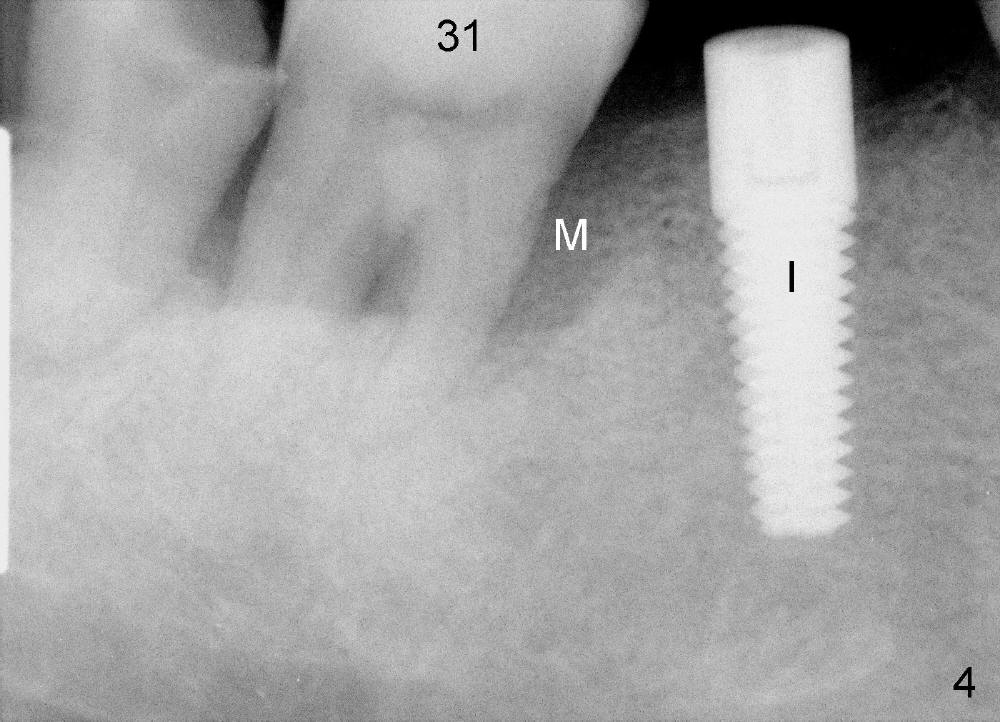

The tooth #31 of a 41-year-old man appears to have combined periodontitis and occlusal trauma: severe mesial bone resorption (Fig.1 (CT sagittal section),Fig.4 (PA)).  In fact, the tooth #32 was extracted when a 5x17 mm implant was placed at the site of #30 (Fig.4).

CT coronal sections at the mesial root of #31 show that a 7x17 (Fig.2) or 7x14 mm (Fig.3) implant does not look too large for the alveolar bone buccolingually.  The large implant is able to help close the large socket (mesial (Fig.1,4) and buccal (Fig.2,3) aspects), reducing the amount of bone graft (red circles) placed.  In contrast, the buccolingual width of #30 is narrower (Fig.9 CT coronal section), allowing a smaller implant (6x17 mm by design (Fig.9), 5x17 mm clinically (Fig.4)).